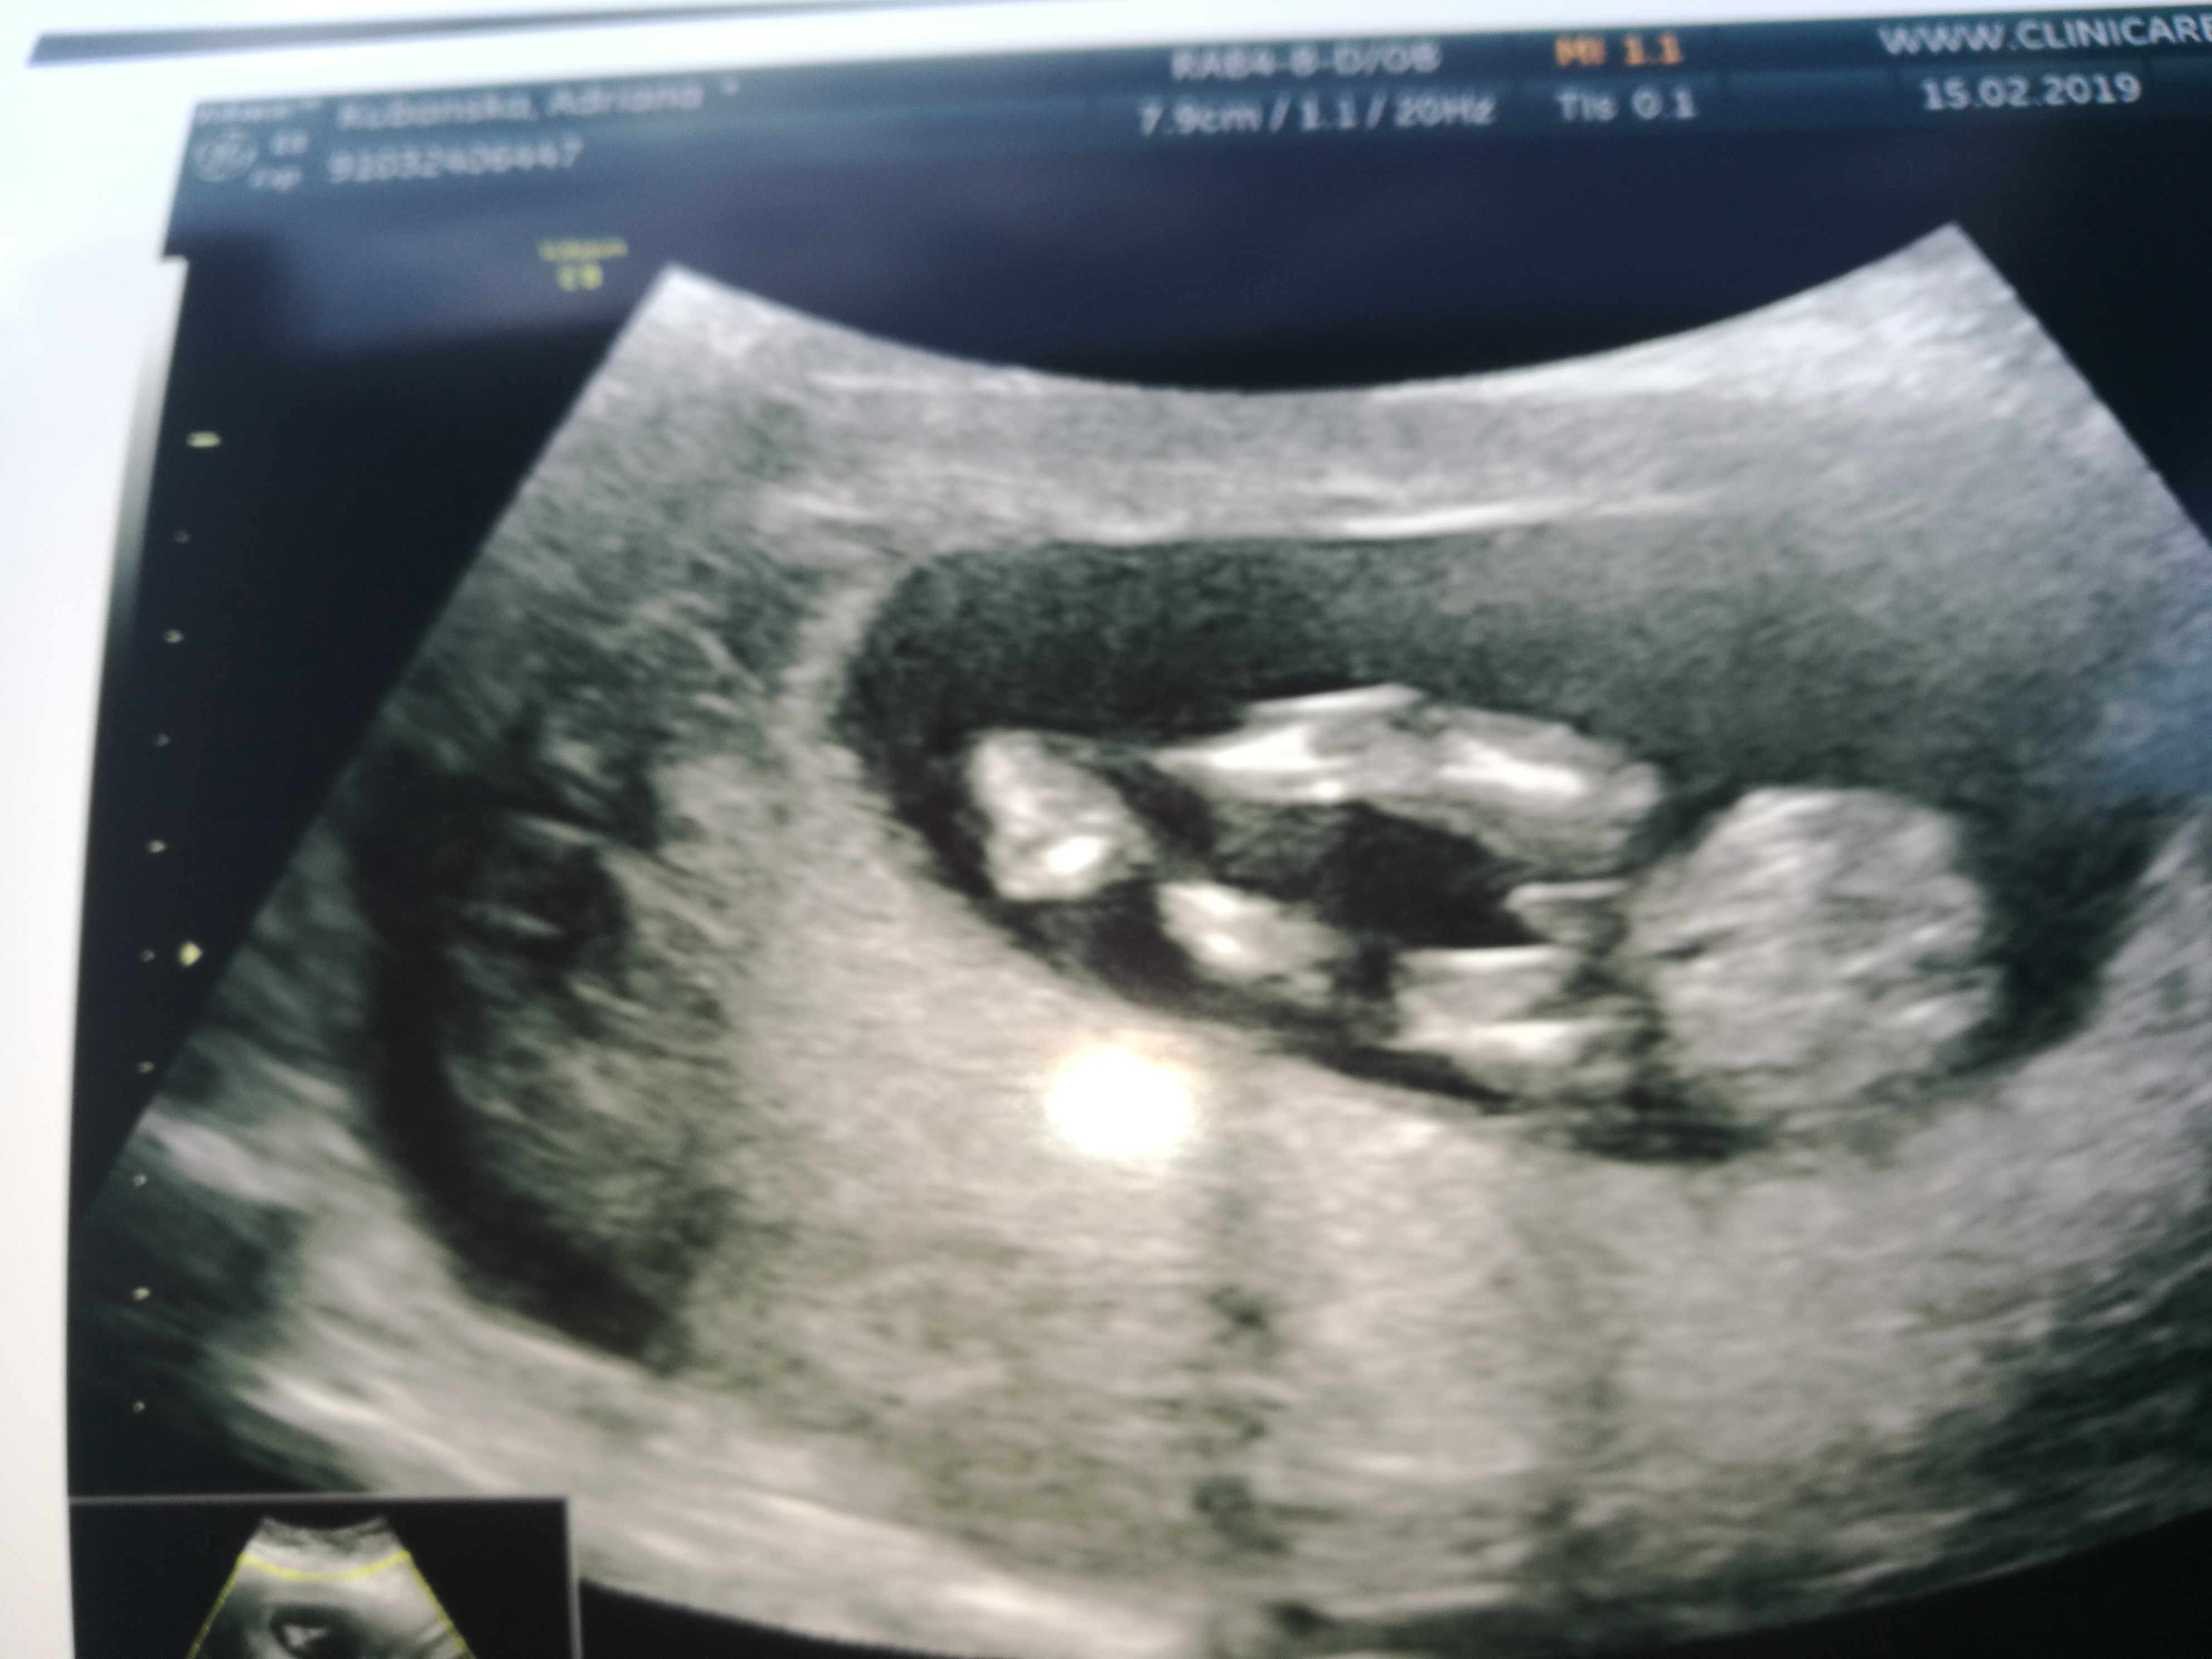

Witam w 19 tygodniu ciąży dowiedziałam się ze będę miała dziewczynkę w 20 tyg okazało się jednak , że to chłopak. Sama już nie wiem bo na jednym usg widać na pewno dziewuche a na drugim chłopca. Może to pempowina ?? Może ktoś mi pomoże rozwiązać ta zagadkę